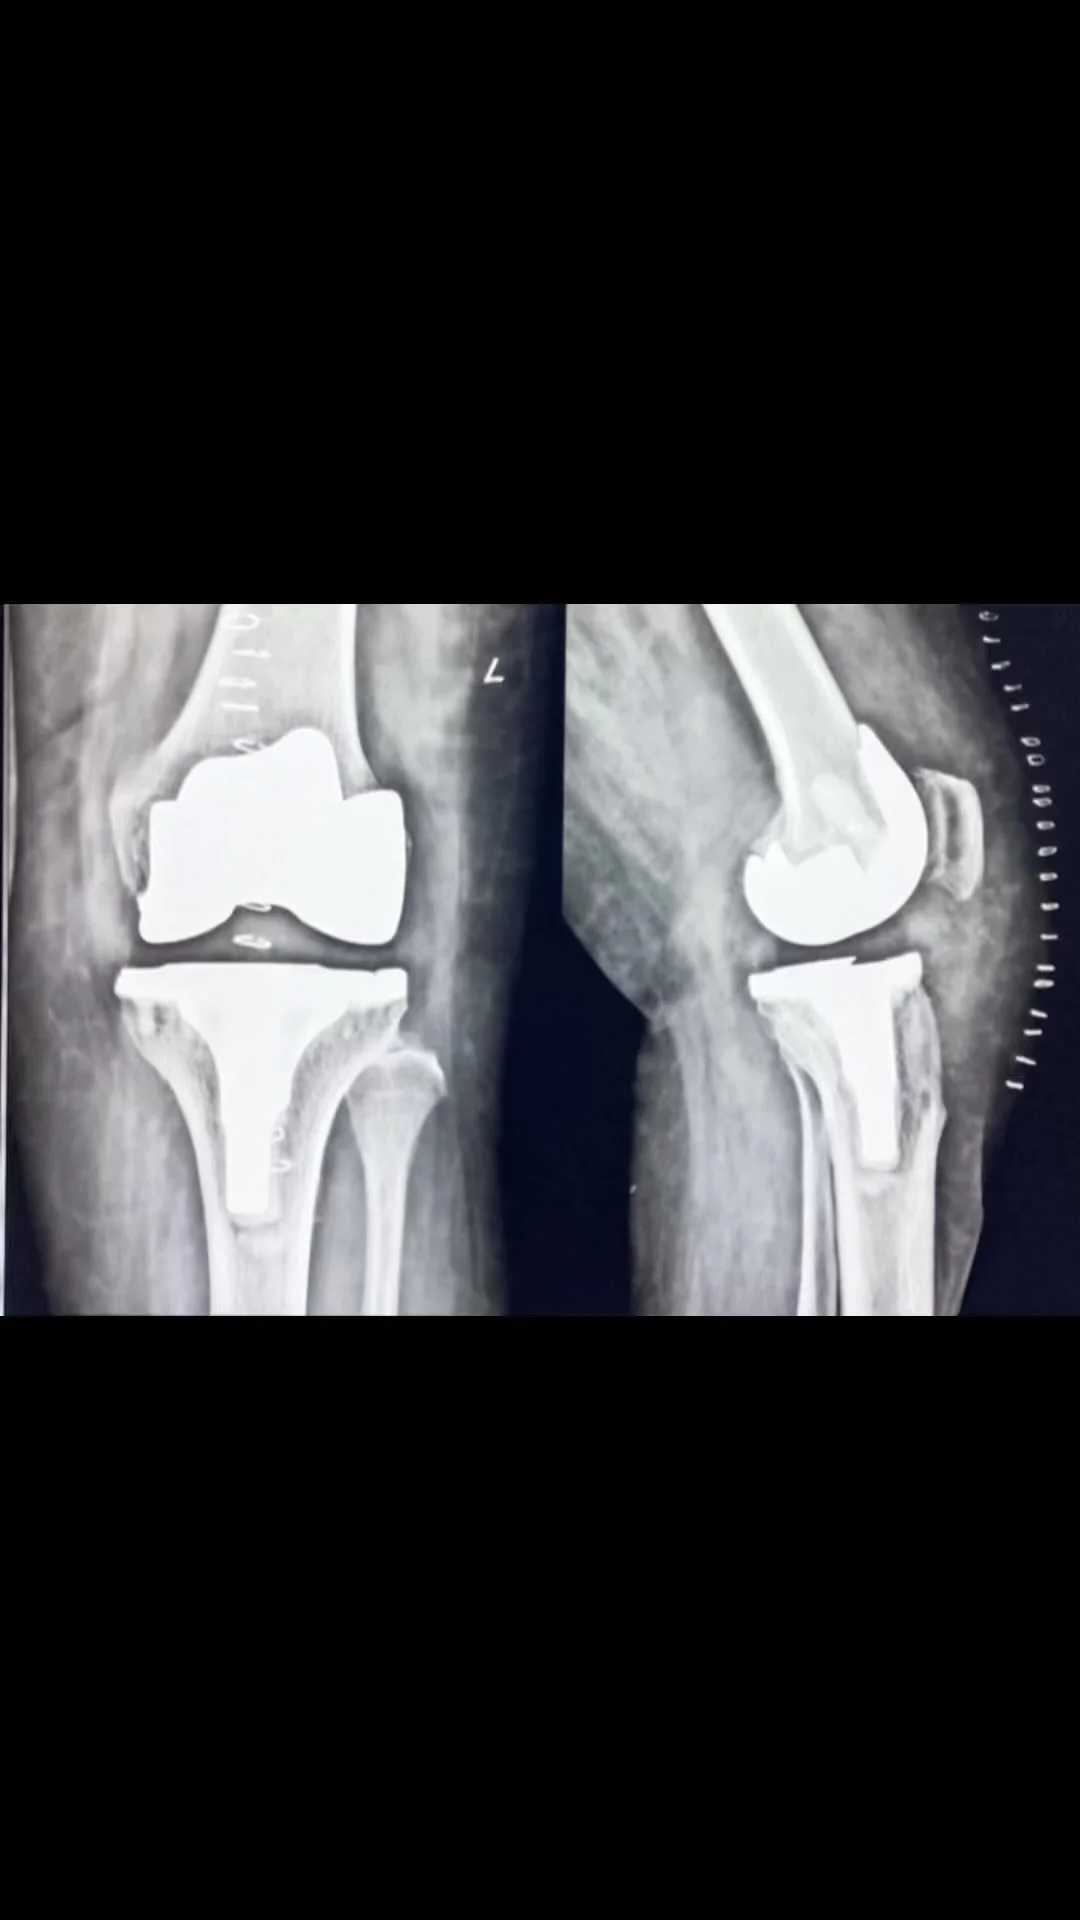

Supporting joint replacement surgeries and medical education. Since starting in 2023, we have come so far⦠View fullsize View fullsize View fullsize View fullsize View fullsize View fullsize View fullsize View fullsize View fullsize View fullsize View fullsize View fullsize